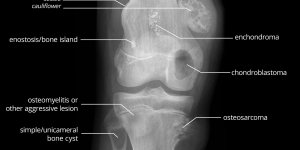

Bone Tumours

Very informative illustration pertaining to Bone Tumours by Matt Skalski @docskalski on twitter. Bone Tumours – Labelled